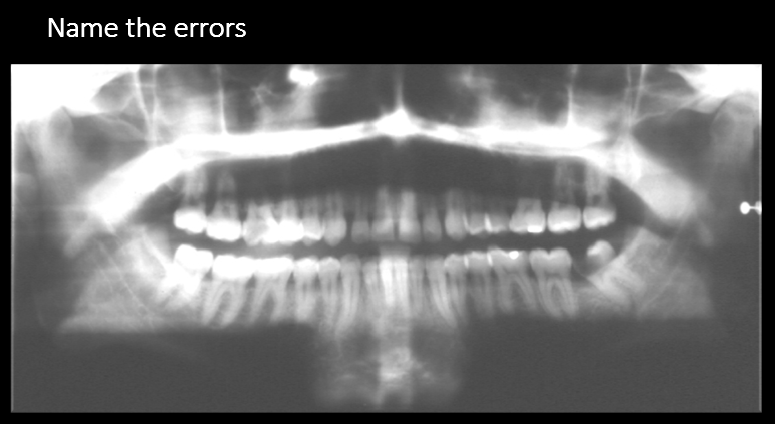

What errors do we see?

A. Chin too high and forward

B. Pt. is laughing

C. Chin too low and head too far back

D. Chin too low and head is too far forward